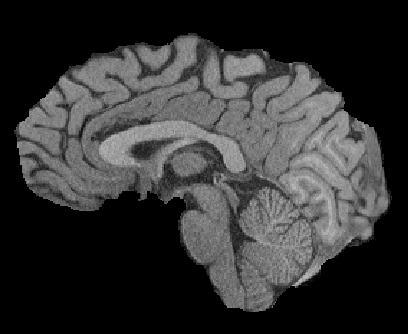

Magnetic resonance (MR) images are often acquired in 2D settings for real clinical applications. The 3D volumes reconstructed by stacking multiple 2D slices have large inter-slice spacing, resulting in lower inter-slice resolution than intra-slice resolution. Super-resolution is a powerful tool to reduce the inter-slice spacing of 3D images to facilitate subsequent visualization and computation tasks. However, most existing works train the super-resolution network at a fixed ratio, which is inconvenient in clinical scenes due to the heterogeneous parameters in MR scanning. In this paper, we propose a single super-resolution network to reduce the inter-slice spacing of MR images at an arbitrarily adjustable ratio. Specifically, we view the input image as a continuous implicit function of coordinates. The intermediate slices of different spacing ratios could be constructed according to the implicit representation up-sampled in the continuous domain. We particularly propose a novel local-aware spatial attention mechanism and long-range residual learning to boost the quality of the output image. The experimental results demonstrate the superiority of our proposed method, even compared to the models trained at a fixed ratio.